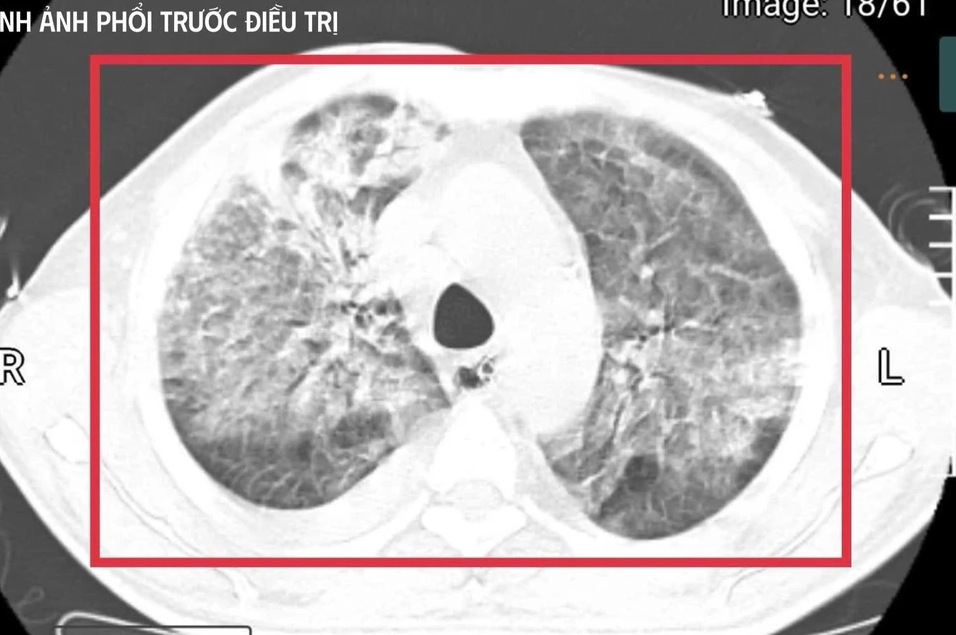

Tại đây, bệnh nhân được đặt nội khí quản thở máy; kết quả cấy máu xác định nhiễm Burkholderia pseudomallei - tác nhân gây bệnh Whitmore. Dù được điều trị ban đầu, tình trạng vẫn diễn tiến nặng nên gia đình xin chuyển về Việt Nam để tiếp tục điều trị.

Xét nghiệm cho thấy men gan và bilirubin tăng cao, rối loạn đông máu, creatinin tăng nhanh kèm vô niệu. Đây là biểu hiện của suy gan, suy thận cấp tiến triển. Nồng độ CK vượt quá 100.000 U/l, kèm đau cơ và nước tiểu sẫm màu, phù hợp với tiêu cơ vân cấp.

Các chỉ số viêm như CRP, PCT tăng rất cao, phản ánh tình trạng nhiễm trùng, nhiễm độc toàn thân dữ dội. Trên nền đó là đái tháo đường chưa kiểm soát và viêm gan C mạn, khiến cơ thể người bệnh càng suy sụp.

Sau khoảng 3 ngày hồi sức cao độ, bệnh nhân bắt đầu cắt sốt, các chỉ số viêm giảm dần, huyết áp ổn định hơn với nhu cầu vận mạch giảm, chức năng gan thận cải thiện, tri giác dần hồi phục. Người bệnh cai được thở máy qua mở khí quản, tập lại hô hấp tự nhiên và phục hồi vận động.